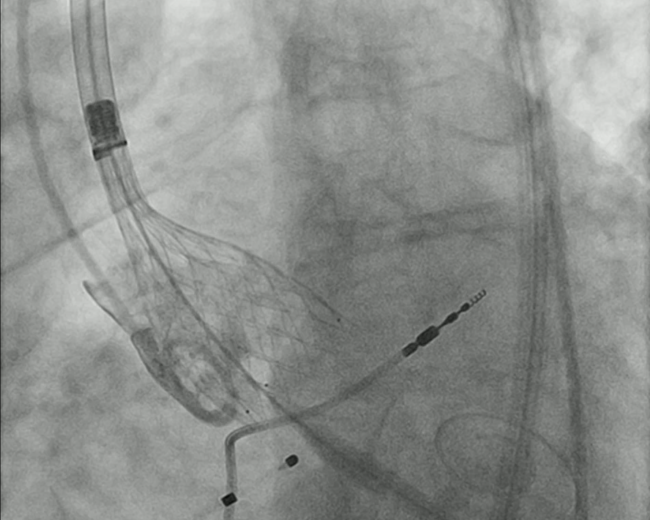

Modified Transcatheter Aortic Valve Replacement: The Pros and Cons of Removing the Guidewire Immediately After Valve Deployment

Video Supplement to "Modified Transcatheter Aortic Valve Replacement: The Pros and Cons of Removing the Guidewire Immediately After Valve Deployment" (Brief Communication).